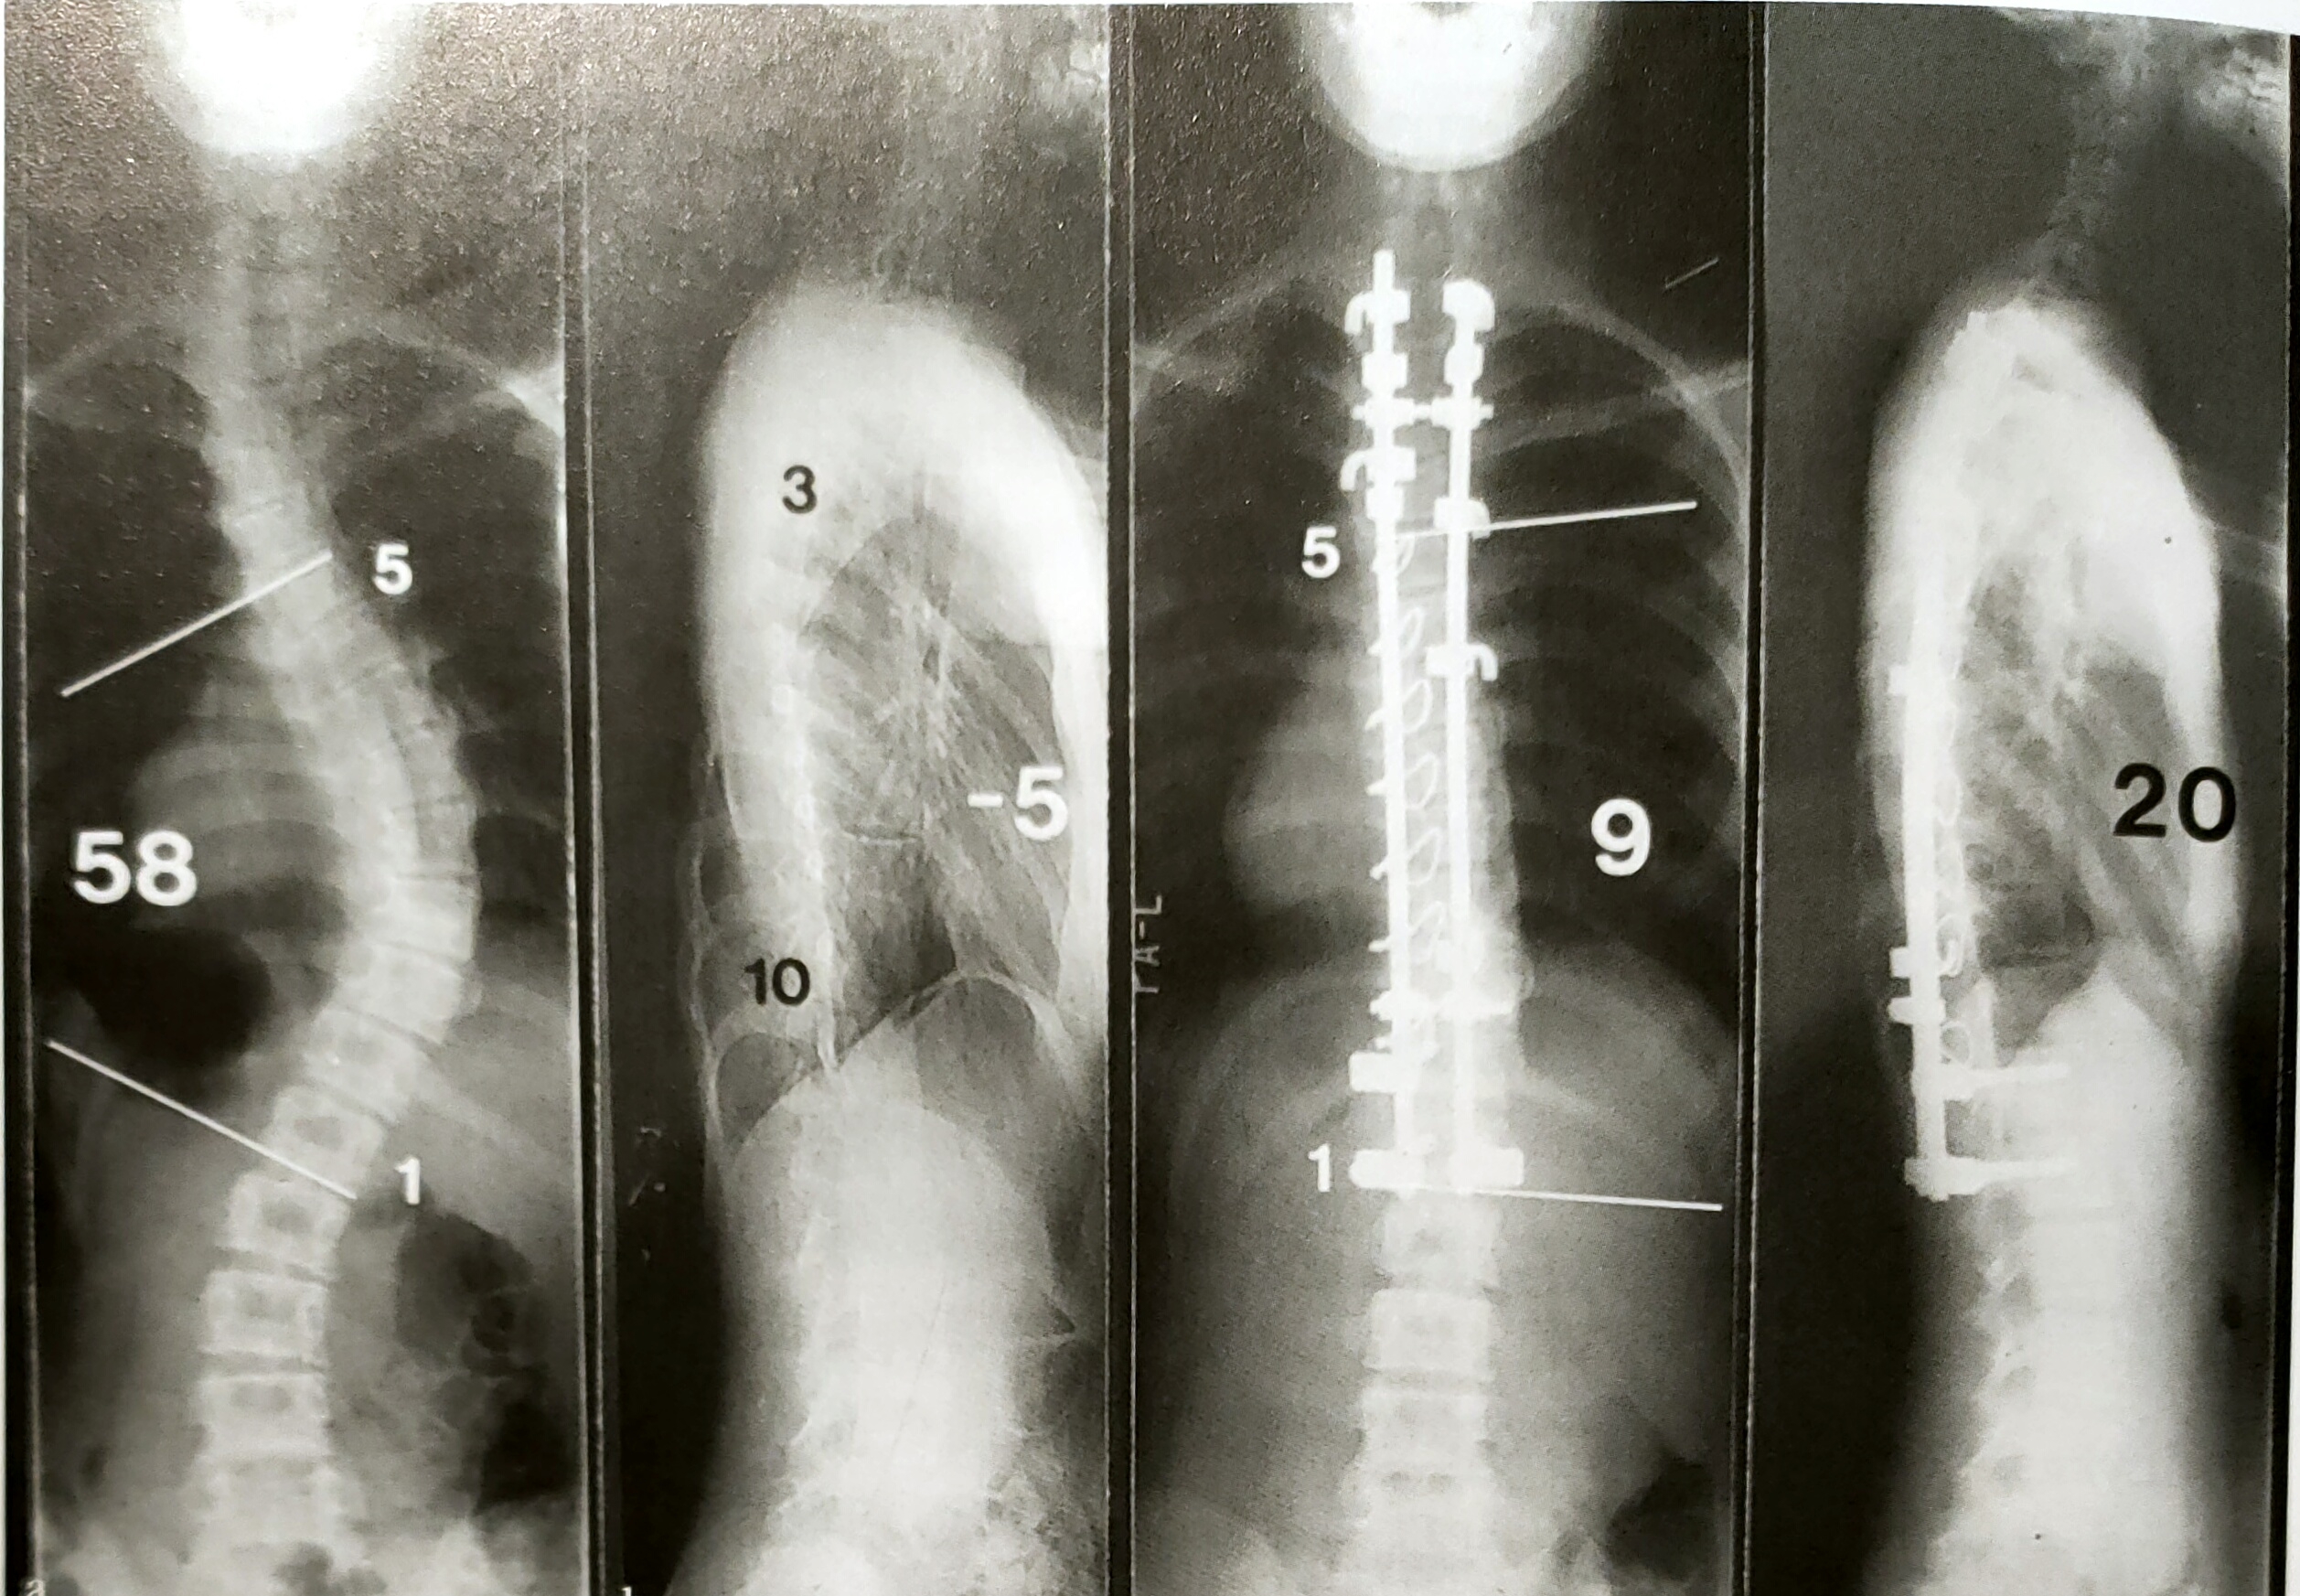

由于椎弓根螺钉系统应用不具有悠久历史,鲜有研究报道其远期临床疗效。Min等报道了48例Lekes 1型和2型青少年特发性脊柱侧凸患者经PS内固定术后的矫正率为55%。这批患者的随访时长为10年。SKK等报道了203例King2、3、4及5型患者,其总体矫正率为69%。有若干研究称,PS内固定术后胸椎后凸角有减小的趋势。然而,Min等和Suk等研究发现PS内固定术后胸椎后凸角不仅不会减小,反而会增大,平均可达5°。2项研究中术后融合率均为100%。而术后10年随访时的功能性临床结果( SRS-24问卷,最高得分120分)为(95+22)分。Min等的研究中再手术率为12.5% (6例患者由于SSI而行植入物移除)。Suk 等则发现在术后早期阶段,SSI的发生率为1.5%,其中有1例患者需要移除植入物。尽管发生了SSI,这些患者在末次随访时仍获得了牢固的骨融合。在此二人的研究中,无一例患者因交界区或神经并发症而需要再次手术。然而,由于全PS内固定系统对侧凸畸形的高矫正率,近年来开始出现PS内固定术后肩部不平衡的相关报道。